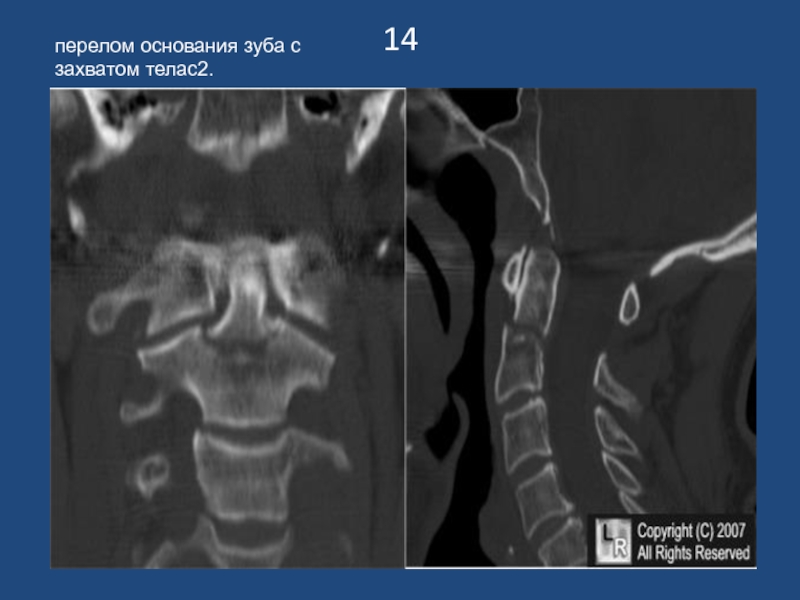

перелом основания зуба с захватом телас2.

14перелом основания зуба с захватом телас2.